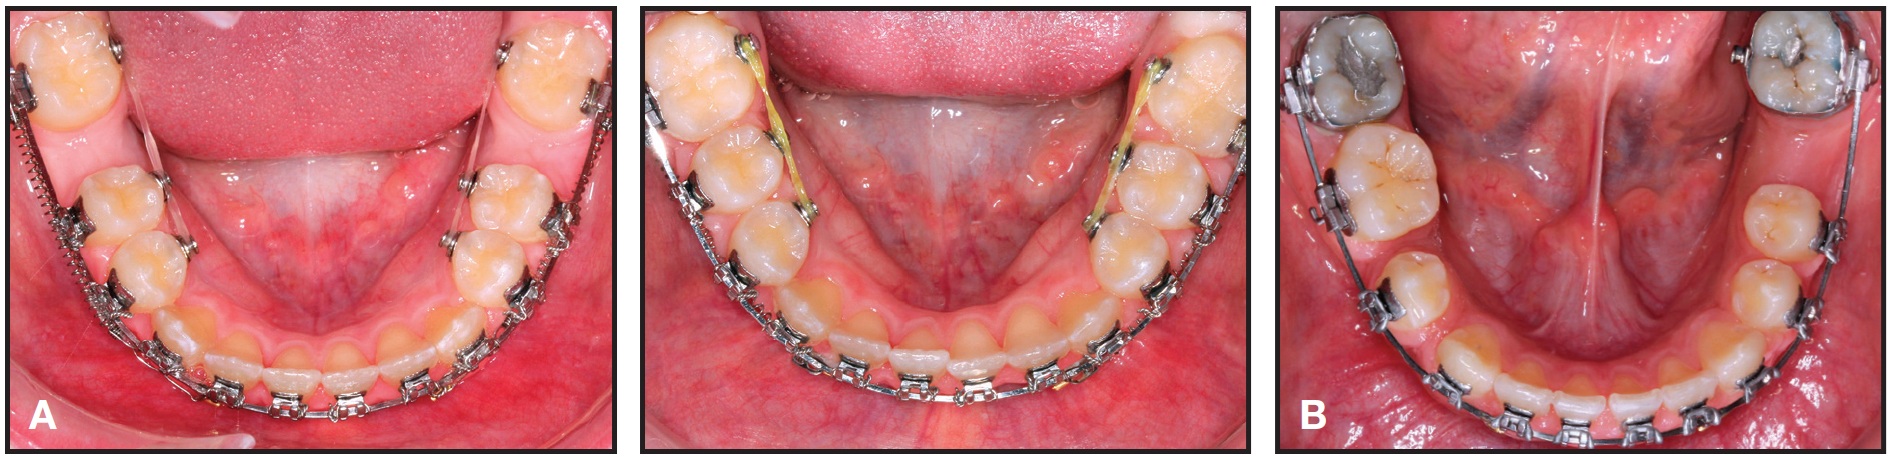

We have found another method that can significantly reduce the time needed for space closure while avoiding undesirable second-molar side effects: double-traction mechanics involving simultaneous lingual and buccal space-closing forces. First, bond lingual buttons to the lower second molar and premolars. Next, attach power chain to the lingual buttons, and add nickel titanium closing coils over the archwires between the second molars and premolars. This approach is demonstrated in a 13-year-old male patient, whose space closure required only four months (A). If bands are used instead of molar tubes, the lingual button can be spot-welded to the band (B).